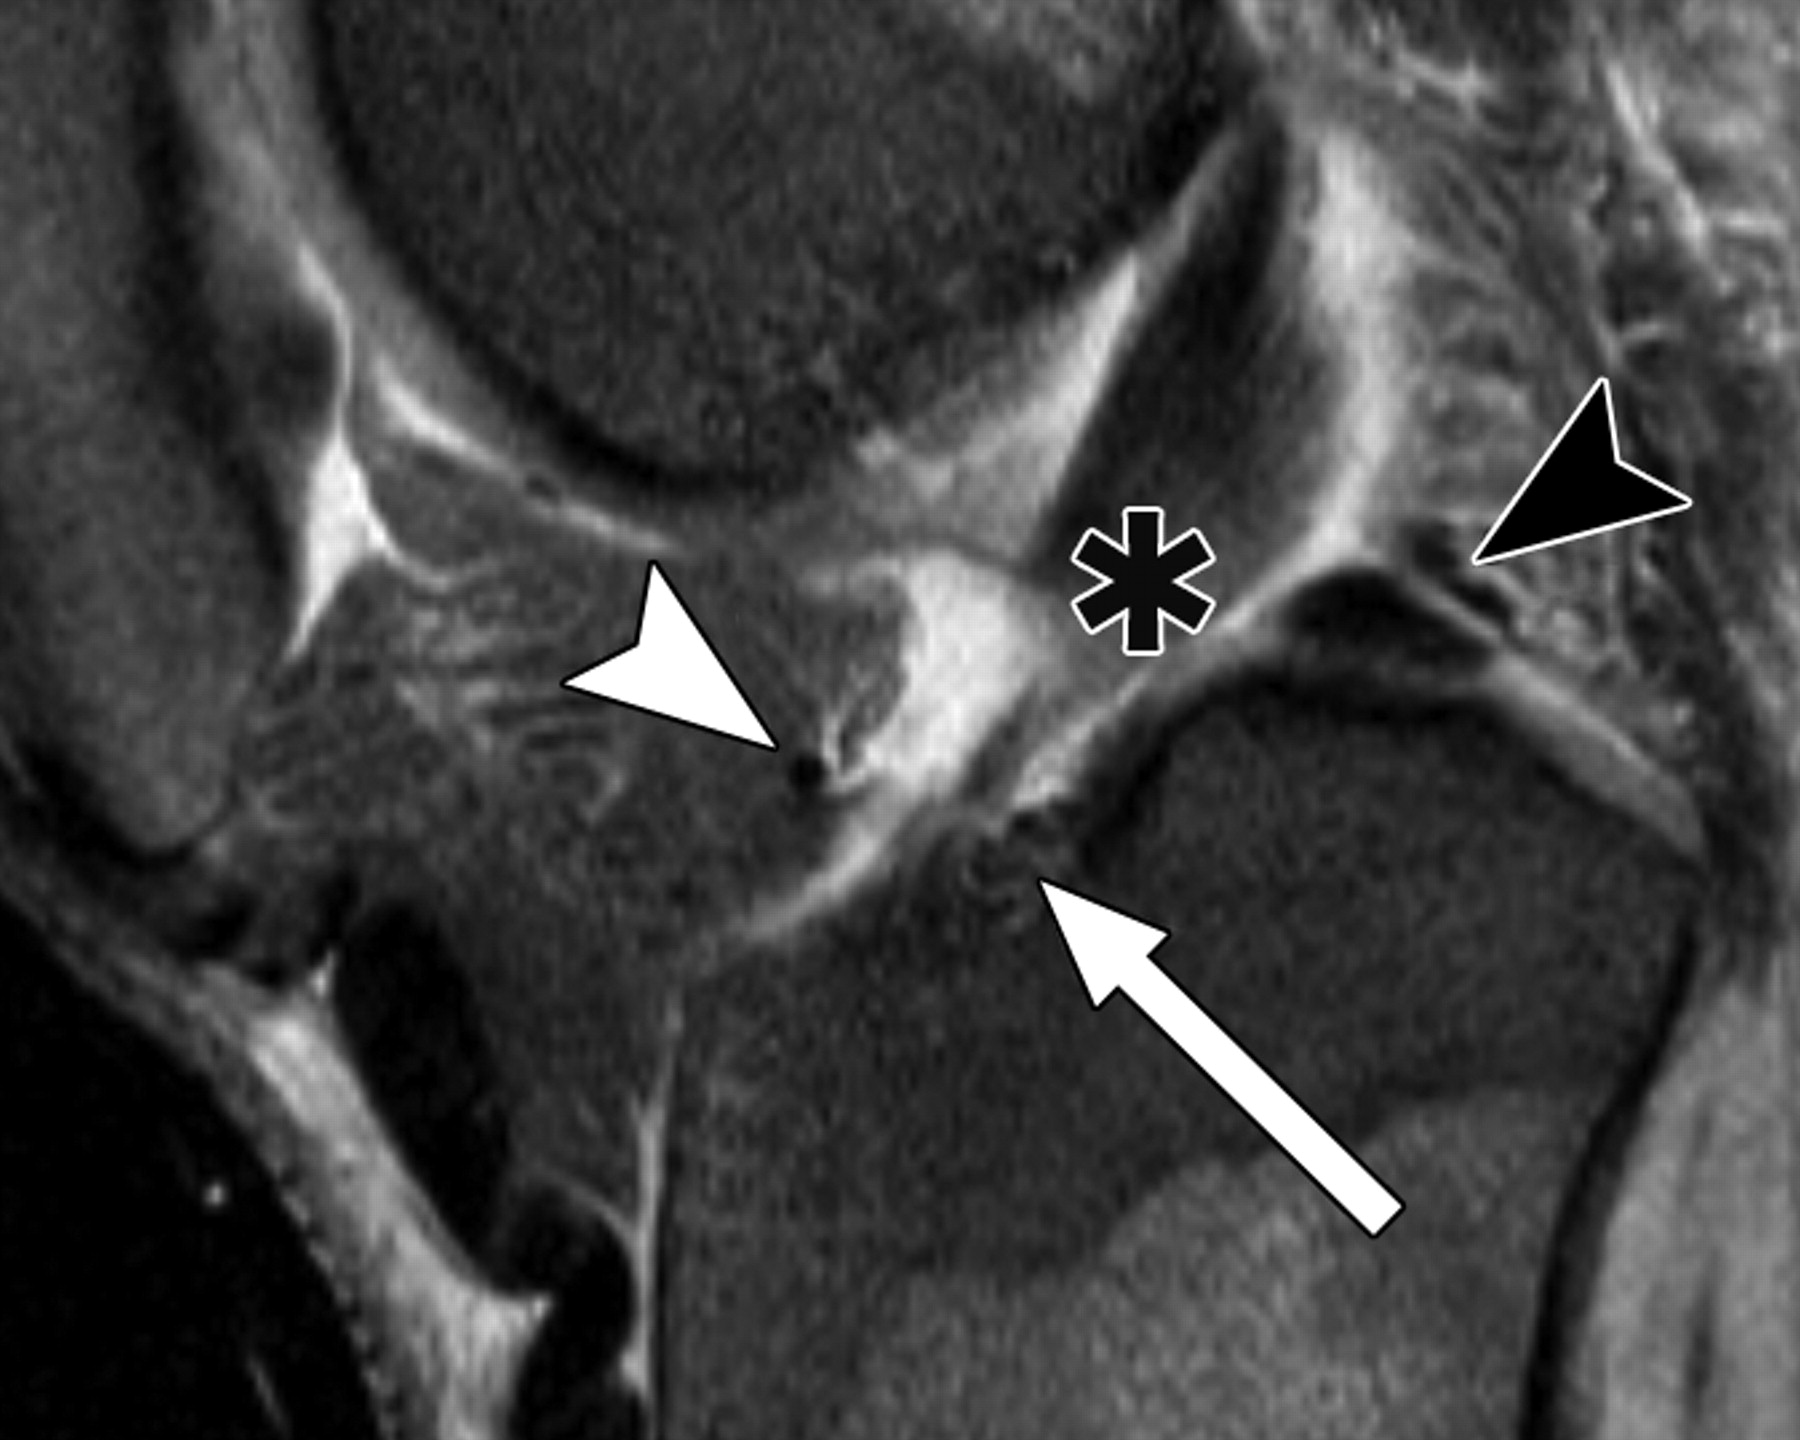

图5A-59岁男性。

中等加权、脂肪饱和、快速自旋回波(TR/TE有效值,3,700/29)3-T MR图像显示半月板后根和交叉韧带的解剖关系。

冠状面MR图像显示内侧半月板(MM)后根(箭头)覆盖后髁间区域的一个以上切片厚度。LM =外侧半月板。LT =胫骨外侧结节。

5520cf3c3107bcbe16a450c0ac30f232.jpeg

图5 B-59岁男性。中等加权、脂肪饱和、快速自旋回波(TR/TE有效值,3,700/29)3-T MR图像显示半月板后根和交叉韧带的解剖关系。

冠状面图像依次位于A的腹侧,显示外侧半月板后根(LM)(白色箭头)和内侧半月板后根(MM)(黑色箭头,B)的插入,覆盖后髁间区域的一个以上切片厚度。MT =胫骨内侧结节。